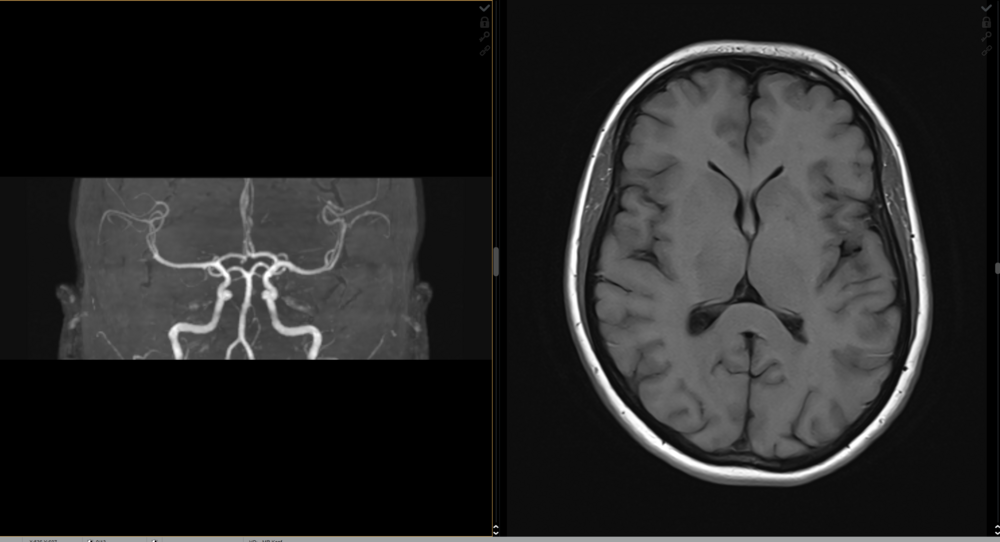

MRT des Kopfes

Bei der Erkennung von Erkrankungen des Gehirns und der Blutgefäße im Kopfbereich kann die Magnetresonanztomographie wichtige Informationen liefern. Sie bietet eine detaillierte Darstellung von Gehirn, Schädel und umgebenden Geweben. Bei häufig wiederkehrenden Kopfschmerzen stellt die MRT einen wichtigen Baustein der Diagnostik dar. Für die Diagnose von Tumoren im Gehirn oder Schlaganfällen werden spezielle MRT-Sequenzen verwendet. Diese Sequenzen sind auf die genaue Visualisierung von Gewebeveränderungen ausgelegt. Die MRT kann sowohl gutartige als auch bösartige Tumore im Gehirn erkennen. Sie ermöglicht die Beurteilung von Größe, Lage und Charakteristik des Tumors, was für die Behandlungsplanung entscheidend ist. Auch Schlaganfälle können durch die MRT frühzeitig erkannt werden. Dies ist wichtig, um schnell die geeignete Therapie einzuleiten und mögliche Schäden zu minimieren.

MR-Angiographie

Die Magnetresonanz-Angiographie (MR-Angiographie) ermöglicht eine präzise Darstellung der Blutgefäße im Körper. So lassen sich beispielsweise die Venen und Arterien im Hals und im Gehirn detailliert abbilden. Dies ist entscheidend für die Diagnose von Schlaganfällen, Aneurysmen oder Engstellen. Auch die präzise Visualisierung der Aorta, der größten Arterie im Körper, ist mittels MRT-Angiographie möglich und dient der Erkennung von Aortenaneurysmen oder anderen Gefäßanomalien. Sie unterstützt durch die Darstellung der Lungenarterien bei der Diagnose von Lungenembolien oder anderen Lungengefäßerkrankungen. Auch die Blutversorgung der Arme und Beine kann durch die MRT-Angiographie untersucht werden, etwa bei Verdacht auf Durchblutungsstörungen oder Gefäßverschlüsse.